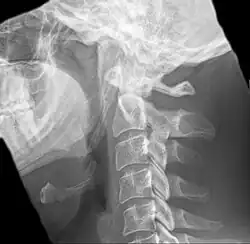

Radiograph, lateral view showing elongated stylohyoid process and stylohyoid ligament ossification -

Imaging is important and is diagnostic. Visualizing the styloid process on a CT scan with 3D reconstruction is the suggested imaging technique.[13] The enlarged styloid may be visible on an orthopantogram or a lateral soft tissue X ray of the neck.